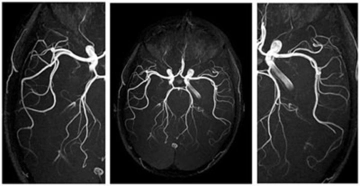

Anjiyo, kalp damarlarının görüntülenmesi için yapılan invaziv bir tanı yöntemidir. Bu işlem, genellikle koroner arter hastalığını değerlendirmek ve tedavi seçeneklerini belirlemek amacıyla gerçekleştirilir. Anjiyo süresi, birçok faktöre bağlı olarak değişiklik gösterebilir. Bu makalede, anjiyo işleminin süresi, aşamaları ve bu süreyi etkileyen faktörler ele alınacaktır. Anjiyo İşleminin AşamalarıAnjiyo işlemi, genel olarak aşağıdaki aşamalardan oluşur:

SonuçAnjiyo, kalp sağlığının değerlendirilmesinde önemli bir rol oynamaktadır. İşlemin süresi, hastanın durumu ve diğer faktörlere bağlı olarak değişiklik gösterebilir. Anjiyo işlemi sonrası hastaların dikkatli bir şekilde izlenmesi, olası komplikasyonların önlenmesi açısından kritik öneme sahiptir. Ek olarak, anjiyo işlemi sırasında ve sonrasında hastaların doktorlarıyla açık bir iletişim kurması, işlem hakkında bilgilendirilmesi ve endişelerinin giderilmesi, hasta memnuniyetini artıracaktır. |